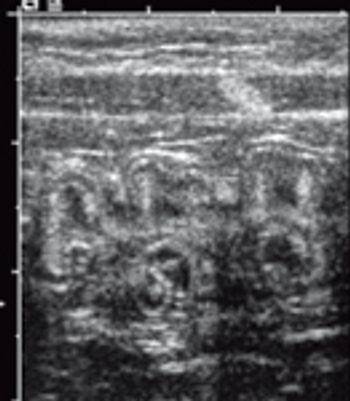

Congenital portosystemic shunts usually are single vessels that develop inside or outside the liver (Photo 1). Because these vessels carry blood around the liver instead of through it, the normal hepatic processes of metabolism, storage and production are disrupted.